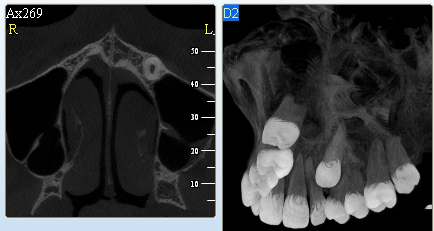

Retinované zuby

Neprořezání (retence) zubu je nejčastější právě u zubů moudrosti a špičáků. Ale i u ostatních zubů se s touto poruchou můžeme občas setkat.

Příčinou je většinou nedostatek místa v čelisti nebo nepřirozená poloha zárodku zubu, někdy nadpočetný zub nebo jizva po úraze.

Nadpočetné zuby

Nejčastěji se vyskytují mezi horními řezáky, ale mohou být i v oblasti dolních řezáků, zubů moudrosti.

Vyšetření pomocí tohoto přístroje používáme i ve stomatochirurgii (zlomeniny čelistí, zuby moudrosti, cysty, onemocnění čelistního kloubu), ortodoncii (retinované zuby, nadpočetné zuby), parodontologii atd.